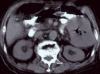

It is very rare that squamous cell carcinoma (SCC) arises from colorectal epithelium. An 89-year-old man was treated in 2001 with chief complaints of anorexia, abdominal pain, and low grade fever. The histological diagnosis as SCC was determined by biopsy during a colonoscopy. We diagnosed primary SCC of the colon because except in the colon no malignant lesions were found by systemic CT. Surgical complete resection was performed. However, he died three months after surgical resection because of hepatic metastasis and cachexia. The prognosis of this disease seems to be worse than that of adenocarcinoma.